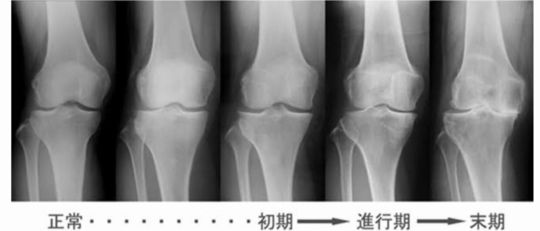

年齢・進行と変形性膝関節症

形性膝関節症の初期は4050代ではじまり、歳を重ねていくごとに変形は進行していきます。

痛みを繰り返すから骨はどんどん変形していき、最終的には末期の変形になります。

病院でレントゲン・CT・MRIを撮って、『膝関節の変形がある。手術しか方法はない!』と医師から言われることがよくあります。

変形性膝関節症の完治は手術しなくてはいけないが、手術前の可動域が術後の可動域の目安になる事はあまり知らない事なので膝関節で悩まれている方は知っておいた方がいい情報になります。